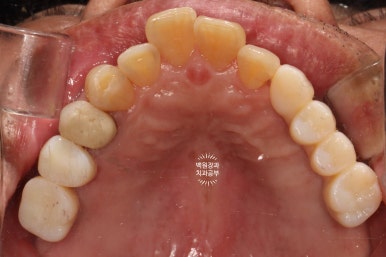

정면 사진입니다.

무면허업자에게 치료 받으셨던 어금니는 이제 하얀 지르코니아 크라운을 가진 임플란트로 대체되었습니다.

아래 틀니는 사라지고, 이젠 고정식의 임플란트로 바뀌었네요!

작은 충치들은 치아색의 레진으로 치료되어, 최종 치료결과는 아주 만족스러움 그 잡채!

위턱 교합면 사진입니다.

오른쪽의 까만색으로 보이는 부위들은 교합조정을 위한 교합종이의 색깔입니다.

충분히 깔끔한 모양새고...

이가 없던 부위는 이가 생겼으니 가장 큰 변화를 이루어냈다고 생각해야겠네요.